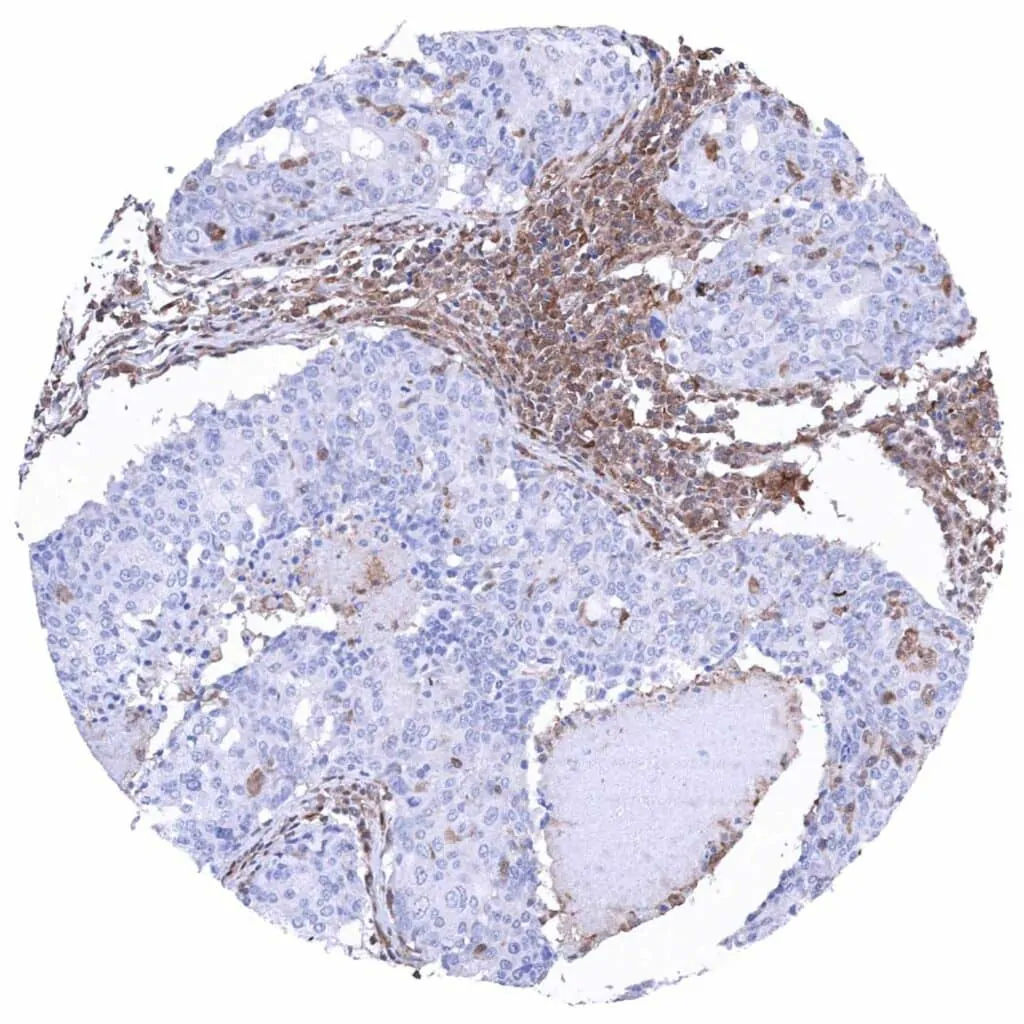

Lymph node – Metastatic malignant melanoma with complete absence of MTAP staining in tumor cells. Distinct MTAP staining of lymphocytes